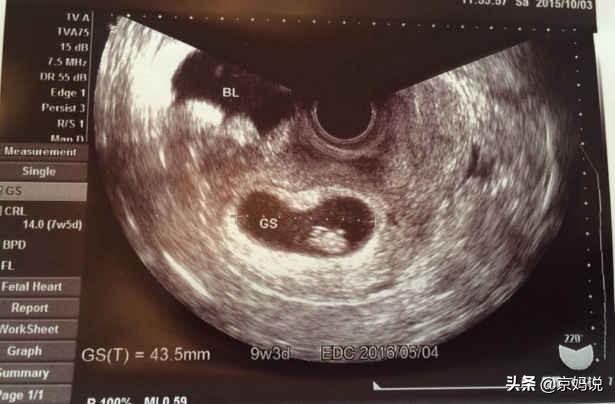

妊娠7~8週目に超音波検査を行い、胎児が子宮内にいるかどうか、胎児の心臓や芽の発育状況を調べることで、母親の気持ちを少し落ち着かせることができる。